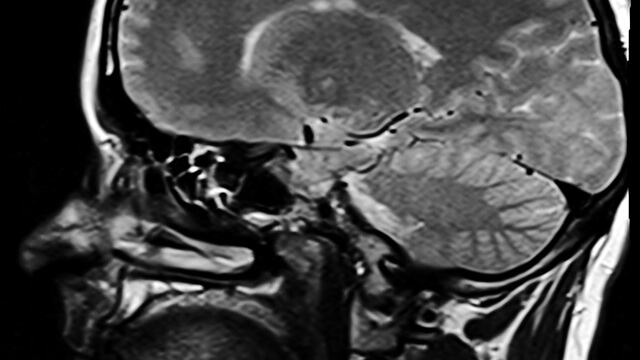

Un grupo de médicos de Canadá investiga nuevos casos de un trastorno cerebral desconocido para la ciencia. De acuerdo con Jennifer Russell, directora médica de la provincia Nuevo Brunswick, hay al menos 43 pacientes de la región que sufren de un nuevo síndrome neurológico progresivo.

Los síntomas de este muevo trastorno cerebral coinciden con la enfermedad de Creutzfeldt-Jakob (ECJ) y sus variantes, incluida la llamada ‘enfermedad de las vacas locas’, pero con algunas alteraciones neurológicas graves.